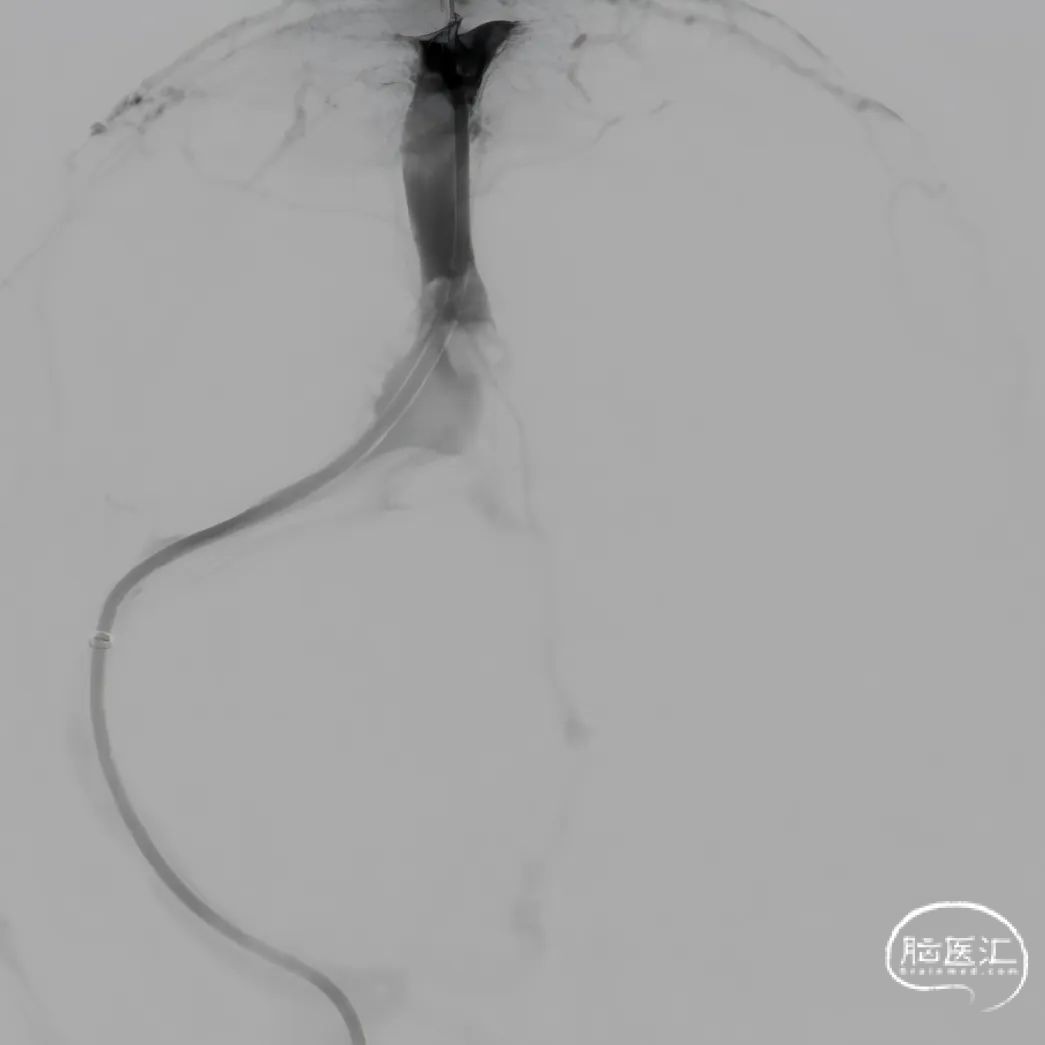

股动脉穿刺置5F鞘做静脉窦造影,股静脉穿刺置8F鞘进行治疗。260cm泥鳅导丝,将132cm 0.068" React™导管送至上矢状窦前部,尽量推高长鞘,增加支撑力。

经中间管手推造影,确认血栓位置。

反复抽吸,多次中间管于负压状态下无回血时,负压状态撤出体外,可见大量血栓。

单纯抽吸难以实现良好再通,经300cm微导丝长交换送入115cm Navien™颅内支撑导管;选用5*30mm球囊扩张,碎栓。

球扩后造影,上矢状窦接触溶栓尿激酶20万U。

球囊扩张和接触溶栓后,再次经中间管反复抽吸后复查造影。

再次给予尿激酶10万U后复查造影。